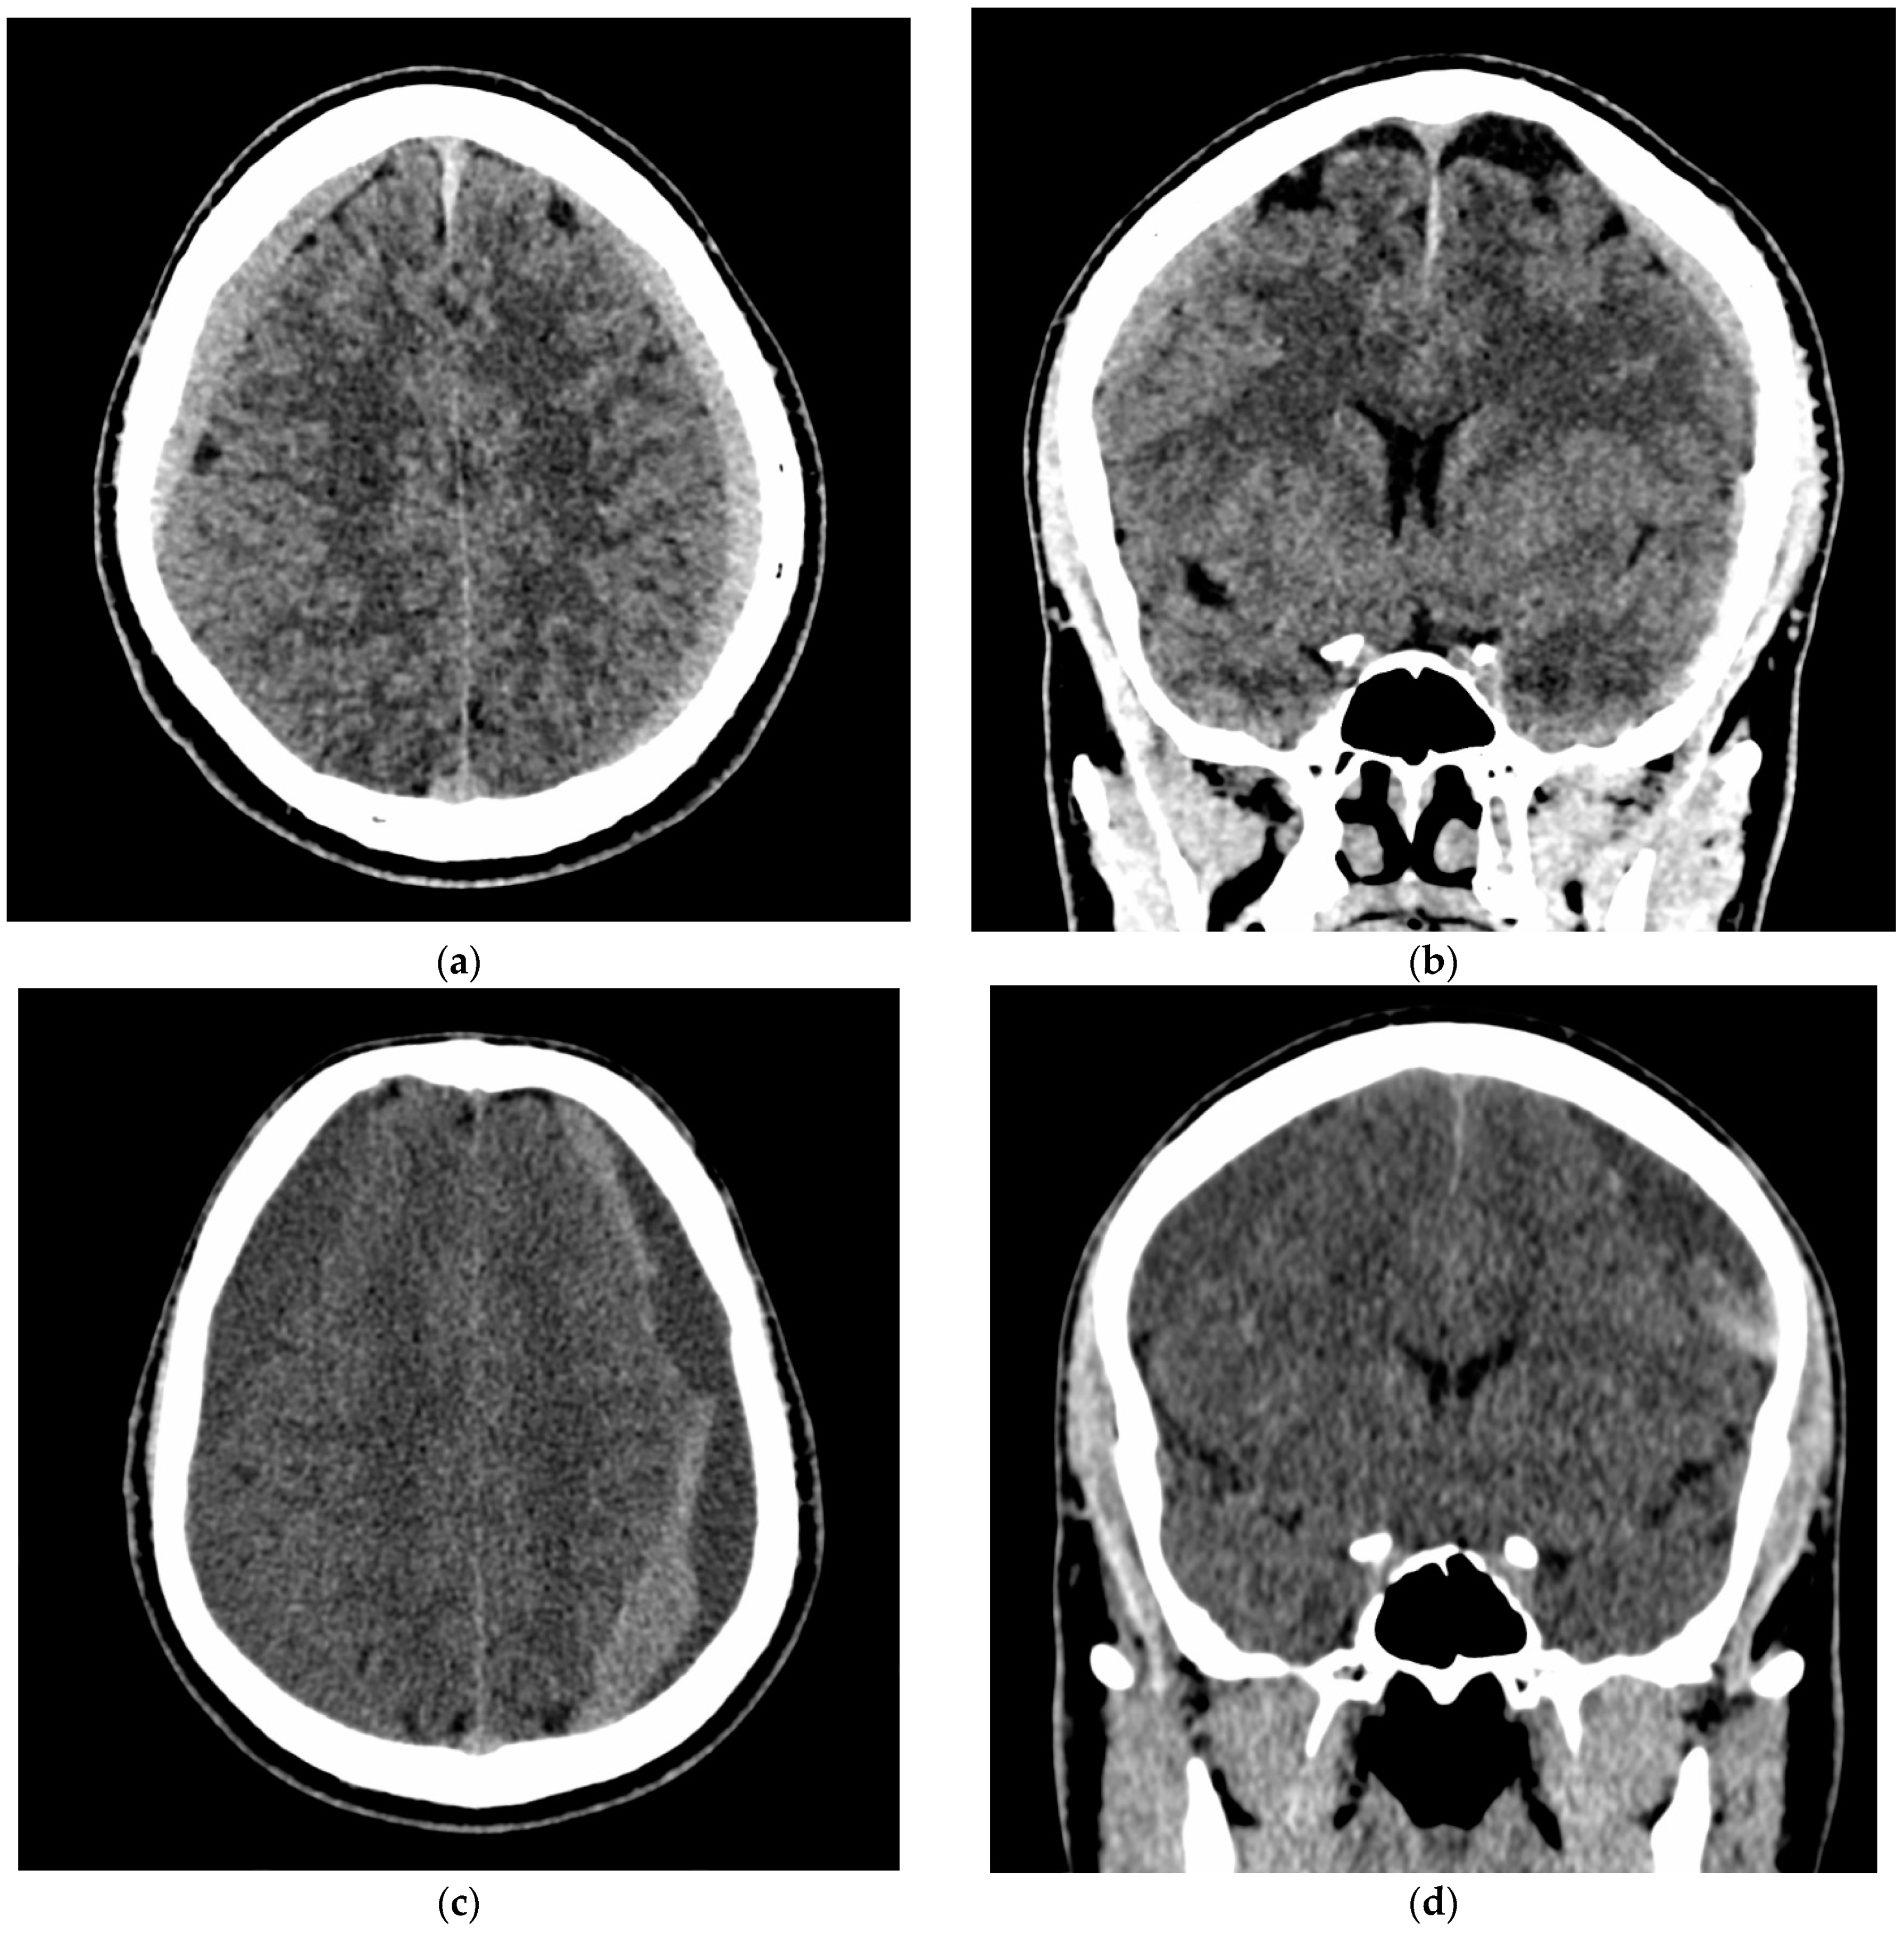

- A 70-year-old patient with left-handed CSDH and a midline shift of 12 mm, motor aphasia, and right-hand hemiparesis.

- A 42-year-old patient with bilateral CSDH that progressively increased during 1.5 months from 54 mL to 69 mL on the right-hand side and from 68 mL to 83 mL on the left-hand side, causing significant compression of both hemispheres and neurological deterioration.

- An 89-year-old patient with bilateral CSDH (no midline shift). There was no apparent connection with an antecedent head injury. However, the patient’s relatives reported that the patient did periodically fall. At the time of admission, the patient presented tetraparesis and a decreased level of consciousness.

3.4. Illustrative Cases